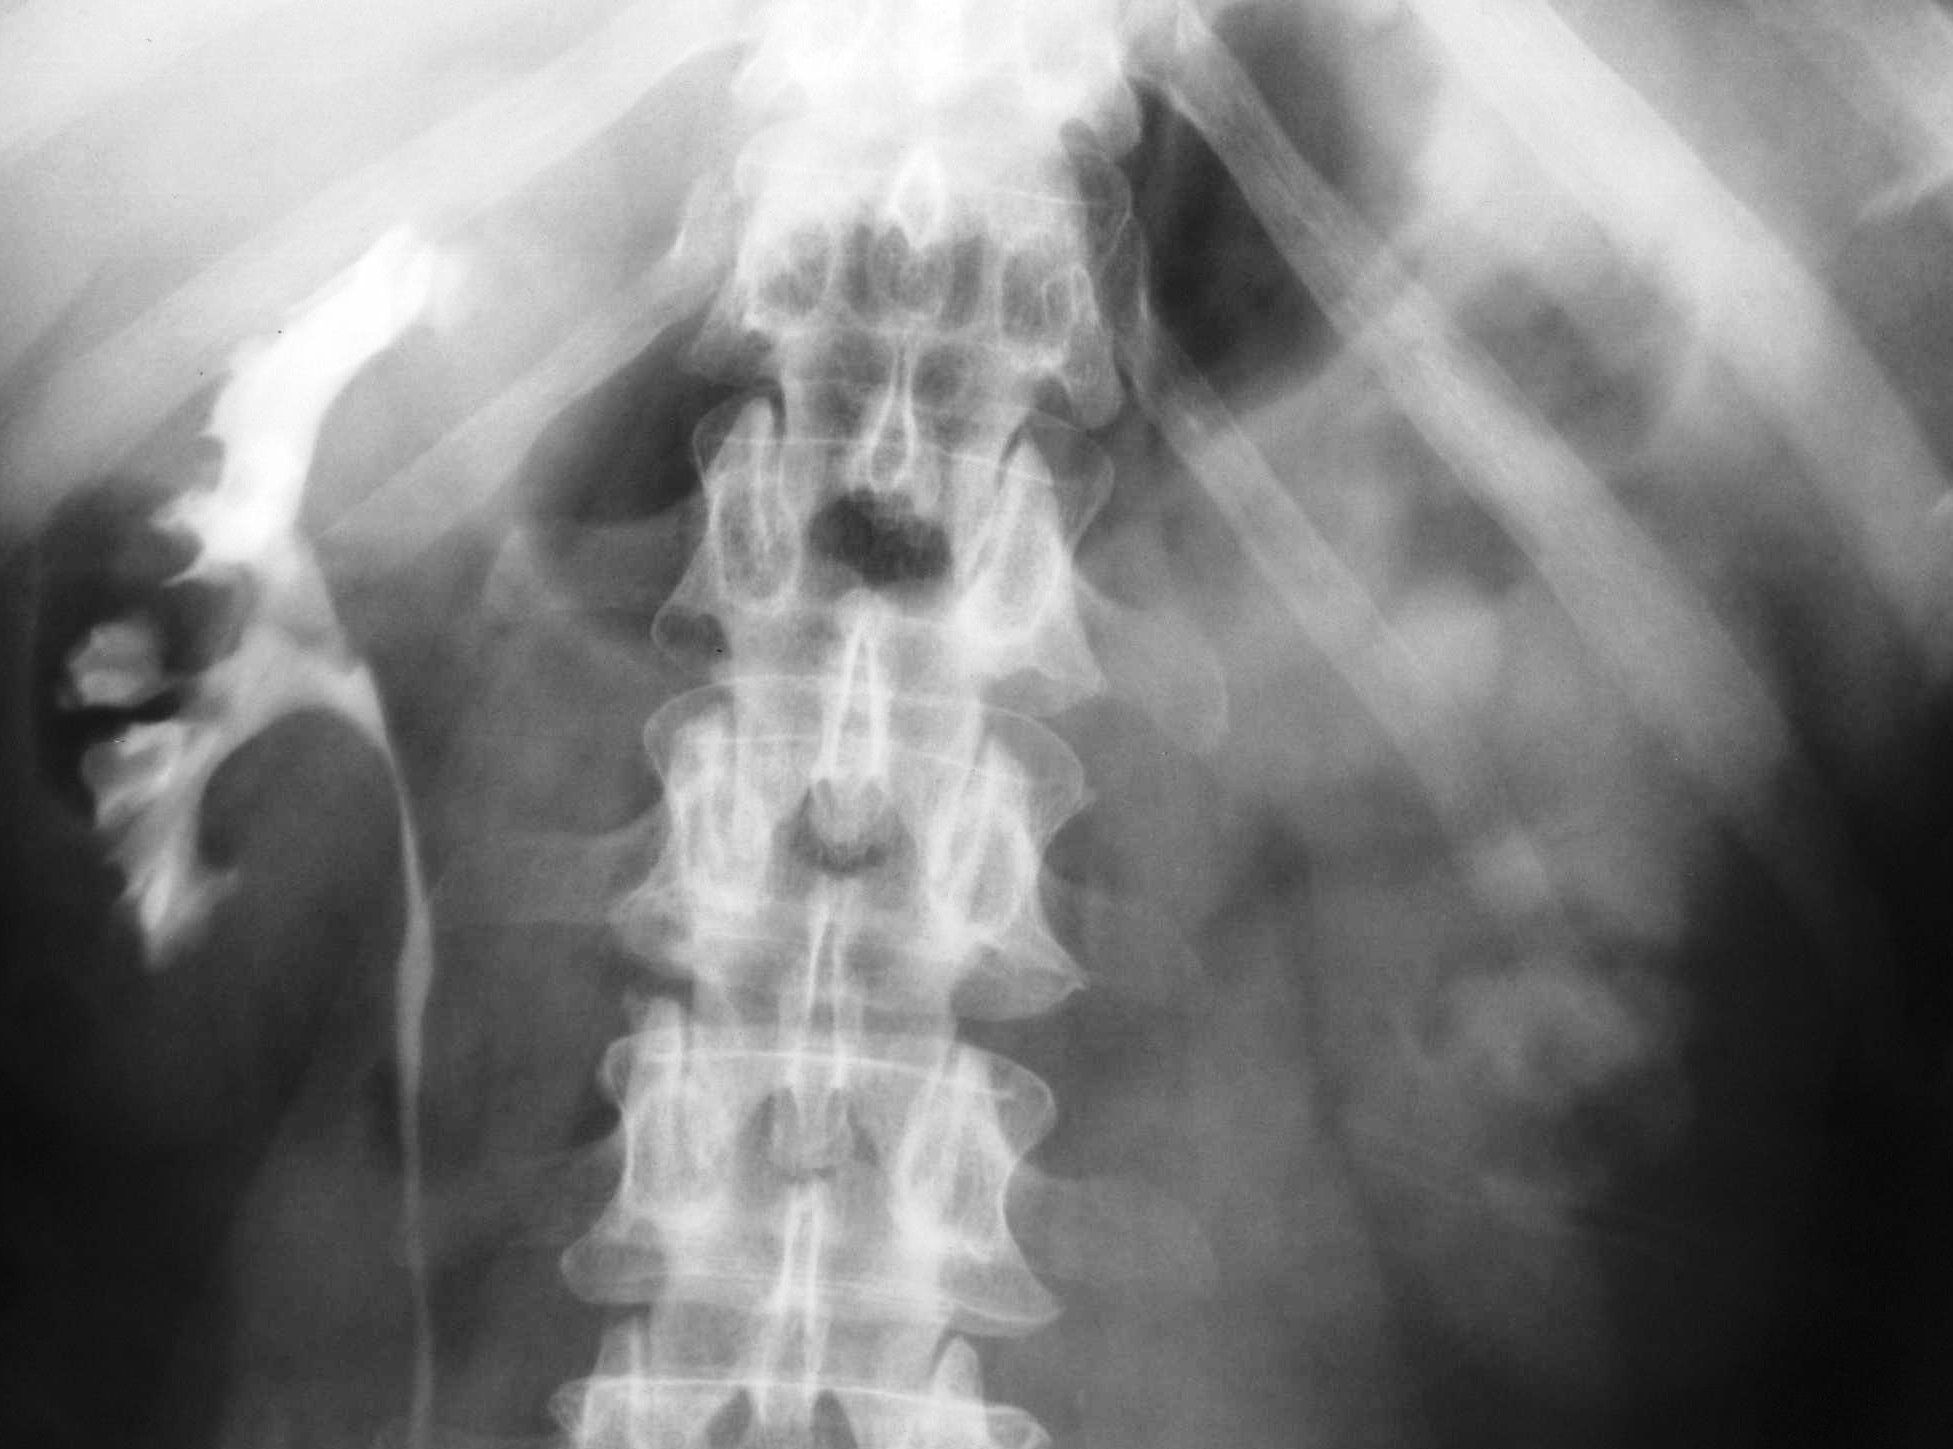

- Figure 4: IVP showing papillary necrosis

- Figure 6: IVP showing hydronephrosis due to ureteric TB